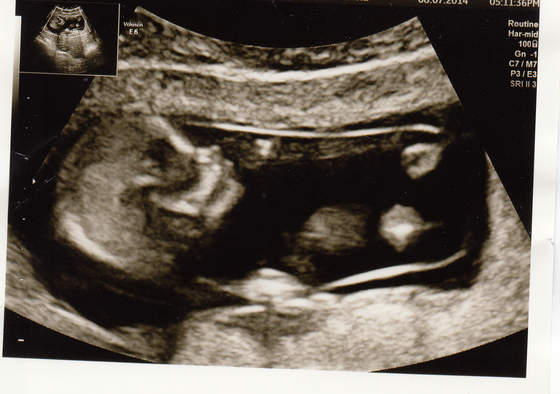

Hej ja po wizycie, bąbel młodszy o 2 dni niz z OM wiec mam sie za tydz pokazac na przeziernosc. Reszta ok, raczki, nozki, zoladek itd itd. Maluch ma 4,84 cm. Ja w pt ide na dokladne usg to moze cosik sie uda podgladnac a na razie taka tylko fotka na szybko. Tak sie wiercil maluch ze nie mozna bylo zrobic ladnego zdjecia